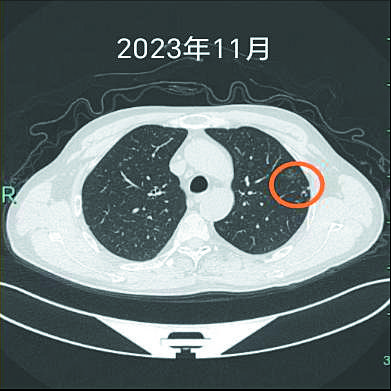

三张图显示,两年间,左上肺的结节越来越明显。

“除了戒烟,还要记得定期复查。”就这样,在术后两年的复查中,医生发现,杨先生的左上肺又出现一个明显的实性结节,并有胸膜牵拉表现,提示有恶性可能。杨先生再次来到该院心胸外科就诊。